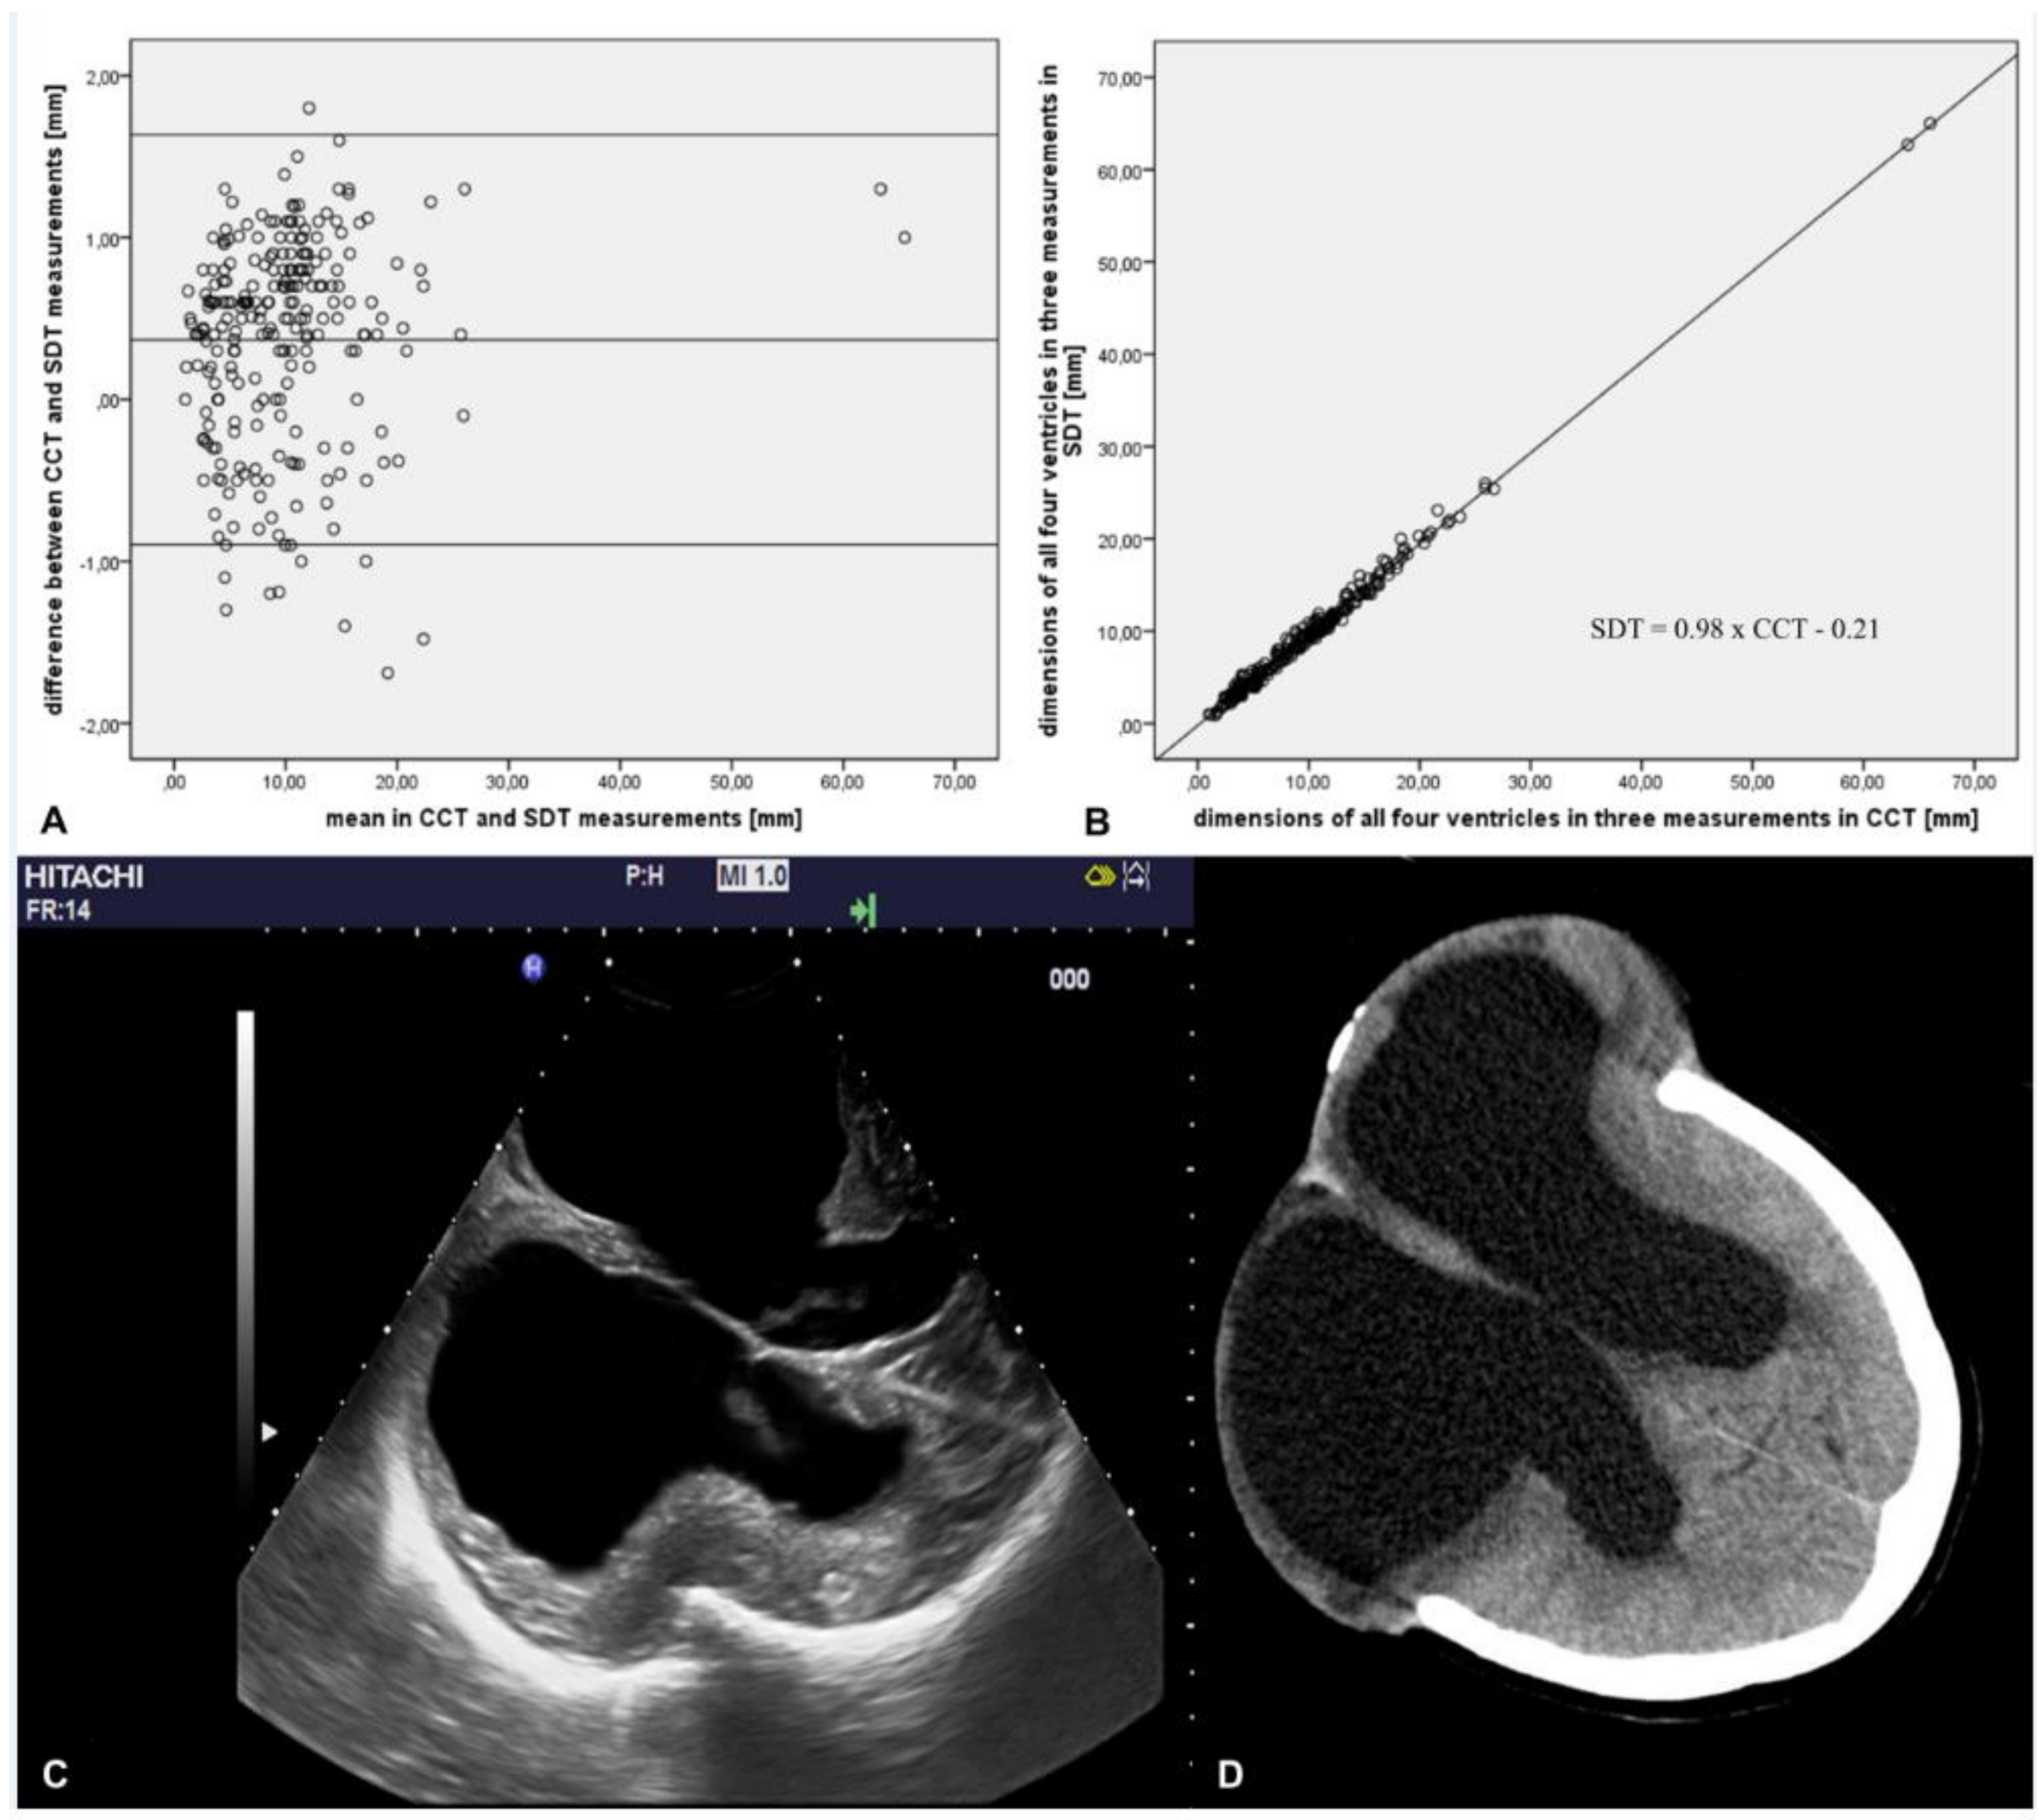

| Measured Structures | Measurement | Cranial Computed Tomography (Mean ± SD in mm) | Sonographic Duplex Technique (Mean ± SD in mm) | Pearson’s Correlation Coefficient r | Pearson’s Correlation Coefficient r for All Three Measurements | Overall Difference with 95% CI |

|---|---|---|---|---|---|---|

| Right lateral ventricle | 1 | 8.1 ± 5.9 | 7.9 ± 5.7 | 0.993* | ||

| 2 | 10.3 ± 5.1 | 9.9 ± 5.1 | 0.995* | 0.997* | +0.3 | |

| 3 | 14.3 ± 13.3 | 13.9 ± 13.2 | 0.998* | [0.1–0.5] | ||

| Left lateral ventricle | 1 | 9.3 ± 5.8 | 9.1 ± 5.9 | 0.990* | ||

| 2 | 11.7 ± 5.9 | 11.3 ± 5.7 | 0.993* | 0.997* | +0.4 | |

| 3 | 15.5 ± 12.7 | 15.0 ± 12.6 | 0.999* | [0.2–0.6] | ||

| Third ventricle | 1 | 4.5 ± 3.2 | 4.3 ± 3.2 | 0.983* | ||

| 2 | 5.7 ± 3.5 | 5.3 ± 3.4 | 0.995* | 0.991* | +0.3 | |

| 3 | 7.4 ± 5.0 | 7.3 ± 4.9 | 0.992* | [0.1–0.4] | ||

| Fourth ventricle | 1 | 10.7 ± 2.6 | 10.3 ± 2.9 | 0.967* | ||

| 2 | 11.3 ± 2.6 | 10.7 ± 2.6 | 0.981* | 0.977* | +0.5 | |

| 3 | 12.3 ± 2.8 | 11.8 ± 2.8 | 0.986* | [0.3–0.6] |